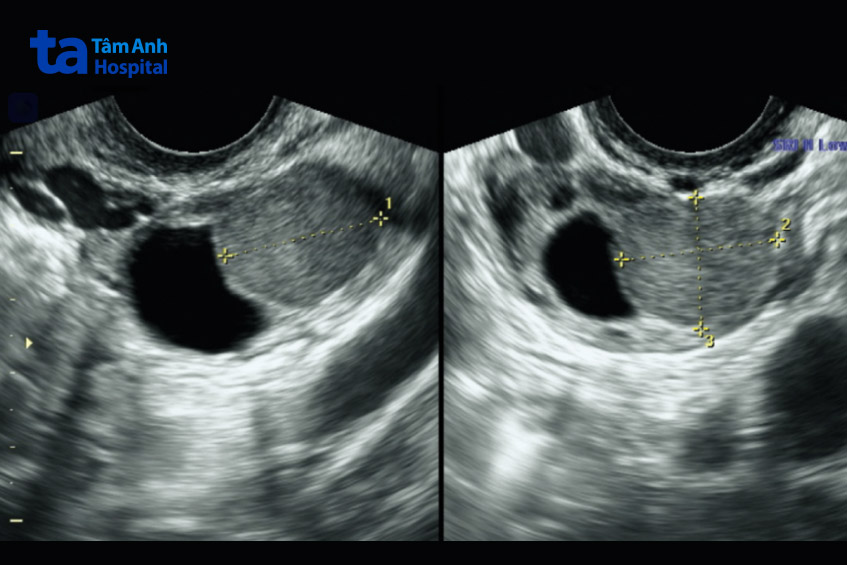

Siêu âm có phát thể hiện lạc nội mạc tử cung bằng việc cho thấy các khối mô lớn hoặc sẹo có khả năng là dấu hiệu của bệnh. Siêu âm có thể xác định bệnh lạc nội mạc tử cung ở buồng trứng nhưng không thể cho thấy các mảnh mô nhỏ (loại lạc nội mạc tử cung phổ biến). Cụ thể, hình ảnh lạc nội mạc tử cung trên siêu âm có thể cho thấy:

Siêu âm lạc nội mạc tử cung bao gồm đánh giá kỹ lưỡng tử cung và buồng trứng bằng siêu âm độ phân giải cao và đầu dò ba chiều, cũng như các cơ quan vùng chậu khác như bàng quang, trực tràng, dây chằng tử cung và âm đạo. Với bệnh lạc nội mạc tử cung siêu âm sẽ thấy các mảnh mô tương tự như mô lót tử cung (nội mạc tử cung) có thể xuất hiện ở những nơi bên ngoài tử cung, như buồng trứng, bàng quang và ruột. Mô không đúng vị trí này có thể bị viêm, phát triển thành u nang hoặc khối u và gây ra các triệu chứng khó chịu, như đau bụng kinh.

Kết quả sau siêu âm có thể cho ra kết quả bình thường hoặc có vấn đề. Khi có vấn đề siêu âm có thể cho thấy các dấu hiệu của bệnh lạc nội mạc tử cung (như sẹo) hoặc cho thấy u lạc nội mạc tử cung hoặc khối u ruột.